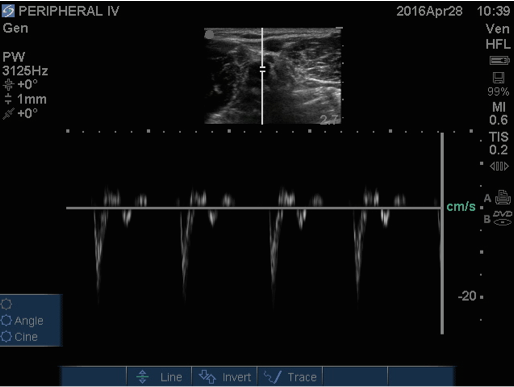

How do you determine the vessel you are looking at is actually a vein? There are many techniques; however, we recommend two methods. First, compress the vessel. Arteries typically continue to pulsate, while veins should easily collapse with minimal pressure (Video 1). Remember that with sufficient pressure one can completely occlude an artery. If you are still not sure, we recommend using spectral Doppler (the one which gives you a waveform (Figure 1). Arterial waveforms will be peaked when compared to the flat waveform of peripheral veins.

Figure 1. Spectral doppler of an artery, showing peaked waveforms.